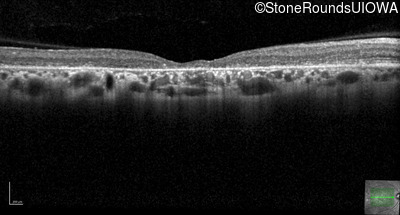

The clinical features favoring the diagnosis of ABCA4-associated autosomal recessive Stargardt disease in this patient include: loss of acuity at the beginning of the second decade, parafoveal photoreceptor loss on OCT, pisciform flecks in the macula with clear peripapillary sparing, and normally sighted parents.

All three of the cardinal ophthalmic features of Mendelian macular dystrophies are present in this patient. The most striking features of the fundus exam are the numerous yellow flecks at the level of the RPE. Flecks are most commonly seen in AR Stargardt disease and pattern dystrophy although they may be seen in some of the rarer Mendelian maculopathies as well. The visual acuity in patients with AR Stargardt disease is often "worse than the fundus looks" while the acuity in pattern dystrophy is often quite good despite extensive flecks. The pedigree of this patient is compatible with ABCA4-associated Stargardt disease and the better than expected acuity is attributable to foveal sparing (see below). The onset of reduced acuity at age 10 is much more characteristic of ABCA4 disease than pattern dystrophy. Another feature present in this patient that is very frequently seen in Stargardt disease is peripapillary sparing. However, this sign can be seen in pattern dystrophy as well. When central atrophy is present in ABCA4-associated Stargardt disease it often somewhat shiny (which is uncommon with the geographic atrophy of pattern dystrophy or age-related macular degeneration). Some patients with ABCA4-associated Stargardt disease can have some preservation of the fovea giving a zonal "bullseye" appearance to the center of the macula. Sometimes this preservation is associated with preserved acuity as in this case. The outer nuclear layer (ONL) is much thinner than normal on OCT, indicative of photoreceptor loss. This is associated with a thinning of the ellipsoid zone which is usually many times brighter and thicker than the external limiting membrane (ELM). These two lines are essentially equal in intensity in this patient. The foveal sparing is seen on OCT only as a small bit of retinal convexity in the center of the atrophy coupled with a small bit of residual RPE flanked by bare Bruch's membrane. The presence of a robust I2e isopter on Goldmann perimetry places this patient in the least severe half of all Stargardt patients (see Schindler, et al., 2010). Most patients with ABCA4-associated disease are somewhat myopic as is this patient. Stargardt patients also tend to perform very poorly on pseudoisochromatic plates, even when their acuity is still fairly good as it is here.